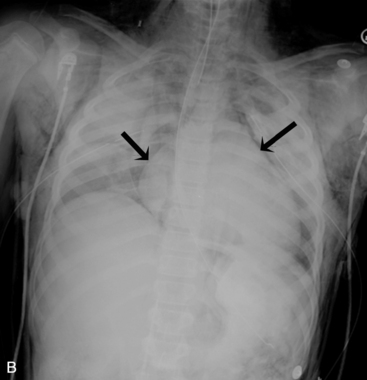

The aortic knob and the trachea will be displaced if a mediastinal shift occurs. When significant atelectasis is present, the trachea and aortic knob usually are displaced toward the area of collapse, because of the volume loss associated with the atelectais.22 However, if a large pleural effusion or pneumothorax is present, the trachea and aortic knob typically will be displaced away from the involved lung and toward the unaffected side, because these problems represent volume gain in the chest (Fig. 10-10).

image

Fig. 10-10 Tension pneumothorax. This 5   month old with complex congenital heart disease was noted by the nurse to have respiratory distress, including tachypnea and nasal flaring. The nurse also noted decreased breath sounds and chest expansion in the left chest and tracheal deviation to the right. This supine anteroposterior film was obtained and demonstrated a left-sided tension pneumothorax (white arrows). The trachea (black arrow) and aortic knob are displaced away from the involved left hemithorax and toward the unaffected right side because of the increased volume associated with the pneumothorax.

The trachea is identified by a straight vertical air density typically just to the right of the patient’s midline. As noted previously, it may appear to buckle to the right on an expiratory film, or it may be displaced toward an area of atelectasis or away from a pneumothorax or pneumomediastinum (see Fig. 10-10). The trachea bifurcates into the right and left mainstem bronchus at approximately the level of the patient’s fourth rib. The carina, a portion of the lowest tracheal ridge, is located at the bifurcation of the trachea and is used as a landmark in radiographic assessment of tracheal tube placement. In adults, the angle of branching of the left main bronchus is normally lower than the angle of branching of the right main bronchus. The right main bronchus typically branches off higher with a sharper angle. For this reason, aspirated substances frequently enter the right bronchial tree.21